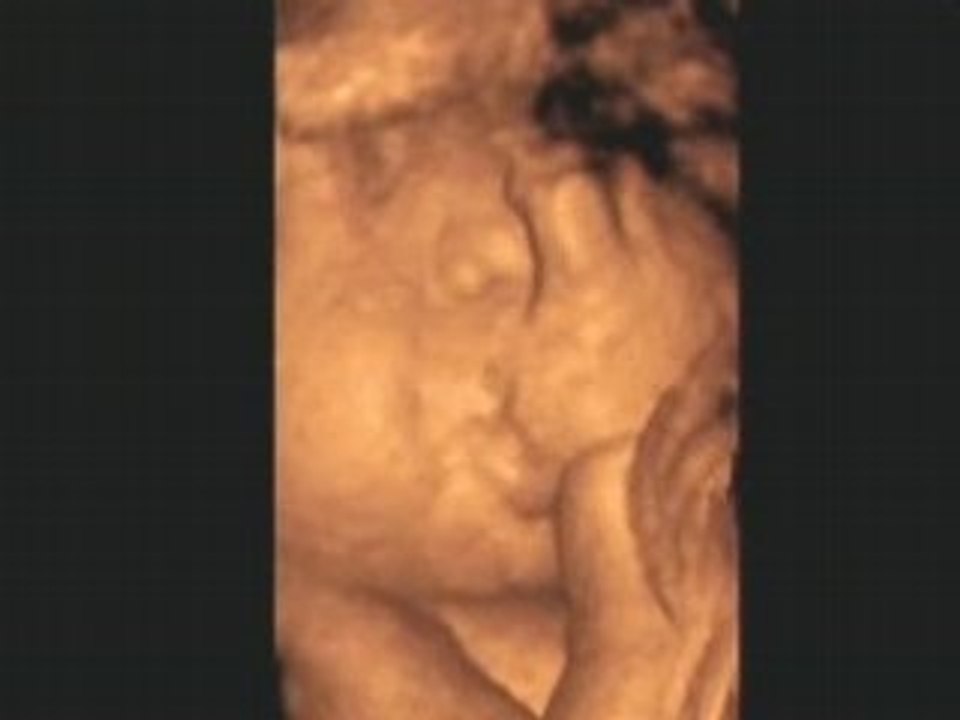

Le monde selon bébé : les sensations du monde 0:47

Le monde selon bébé : les sensations du monde

Le monde selon bébé : un monde de sensations 1:00

Le monde selon bébé : un monde de sensations